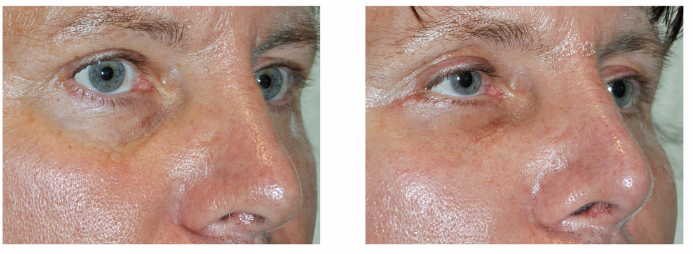

Fat Grafting

Fat grafting restores volume loss in the face, including both upper and lower eyelids, tear troughs, cheeks, and temples.Overview

Fat is harvested from areas like the abdomen or thighs.The fat is processed and purified.

Small injections are made into the target areas to restore volume and smooth contours.

Pros:

Natural filler using your own tissueImproves hollows, wrinkles, and facial symmetry

Minimal risk of allergic reaction

Cons:

Some fat may be resorbed over time, requiring touch-upsSwelling and bruising for 1–2 weeks

Requires experience to avoid lumps or irregularities

FAT GRAFTING BEFORE & AFTER

Price: €1,000–€4,000